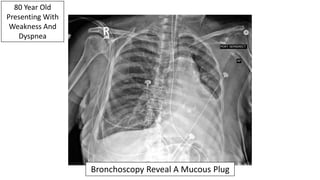

80 Year Old

Presenting With

Weakness And

Dyspnea

Left Mainstem Obstruction: Neoplasm Vs. Mucous Plug

Bronchoscopy Reveal A Mucous Plug